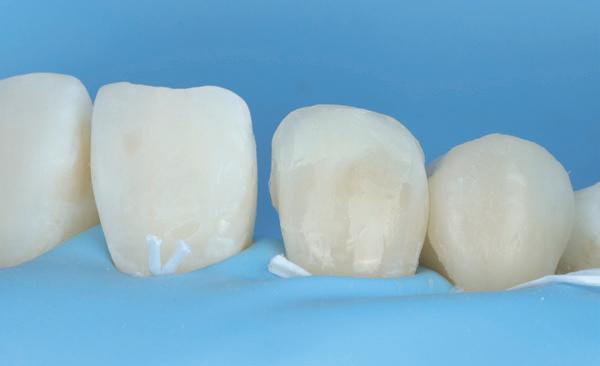

Voordat er gescand kon worden voor een etsbrug, werd een studiemodel vervaardigd om met de technicus te overleggen of er voldoende ruimte was voor 2 centrale incisieven in de mesio-distale zin en of er voldoende ruimte was in occlusie voor de vleugels van de etsbrug. Er hoeft enkel nog aan de 12 en 22 pala-

tinaal geslepen te worden als er geen 1,5 mm ruimte voor de vleugels behaald kan worden. De ruimte was op de dunste plekken 1 mm, dus een kleine preparatie in de 12 en 22 palatinaal was nodig. Omdat de kaak volledig afgevlakt was en dun was geworden, kunnen de dummies van de etsbrug enkel op de kaak “gelegd worden”, maar daarbij zijn er geen papillen en staat de cervicale rand van de dummies net voor de kaak. Een esthetisch resultaat kan daarmee niet behaald worden. Daarom is een aanvulling van de zachte weefsels in de breedte nodig, als het creëren van een emergence profile, waarbij het oogst alsof de gebitselementen uit het weefsel vertrekken.

18. Etsbrug frontbeeld

19. Etsbrug palatinaal